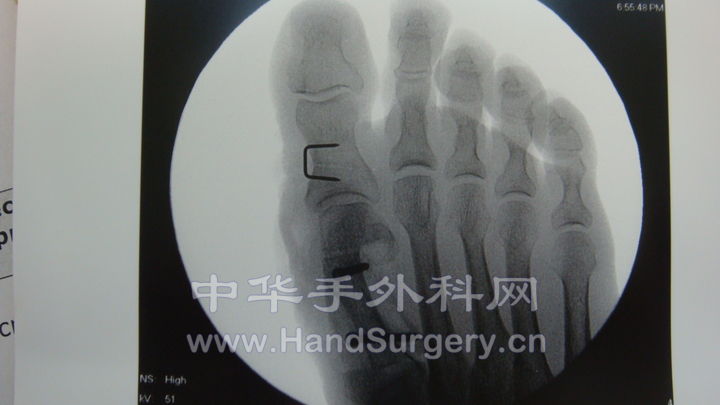

chevron截骨